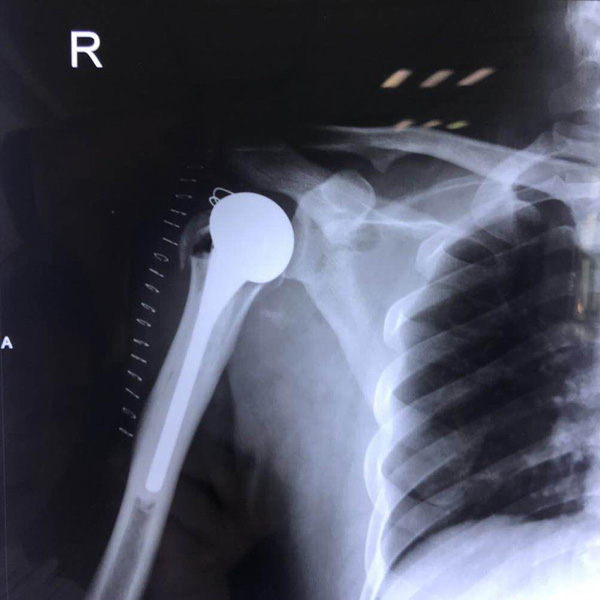

右側(cè)肱骨頭置換

患者郭某,男,40歲,因嚴(yán)重車(chē)禍導(dǎo)致“右肱骨頭粉碎性骨折”,一般的手術(shù)很難將粉碎的骨折塊拼接起來(lái),即便大致的拼接起來(lái),因?yàn)楣敲娴牟黄?.....